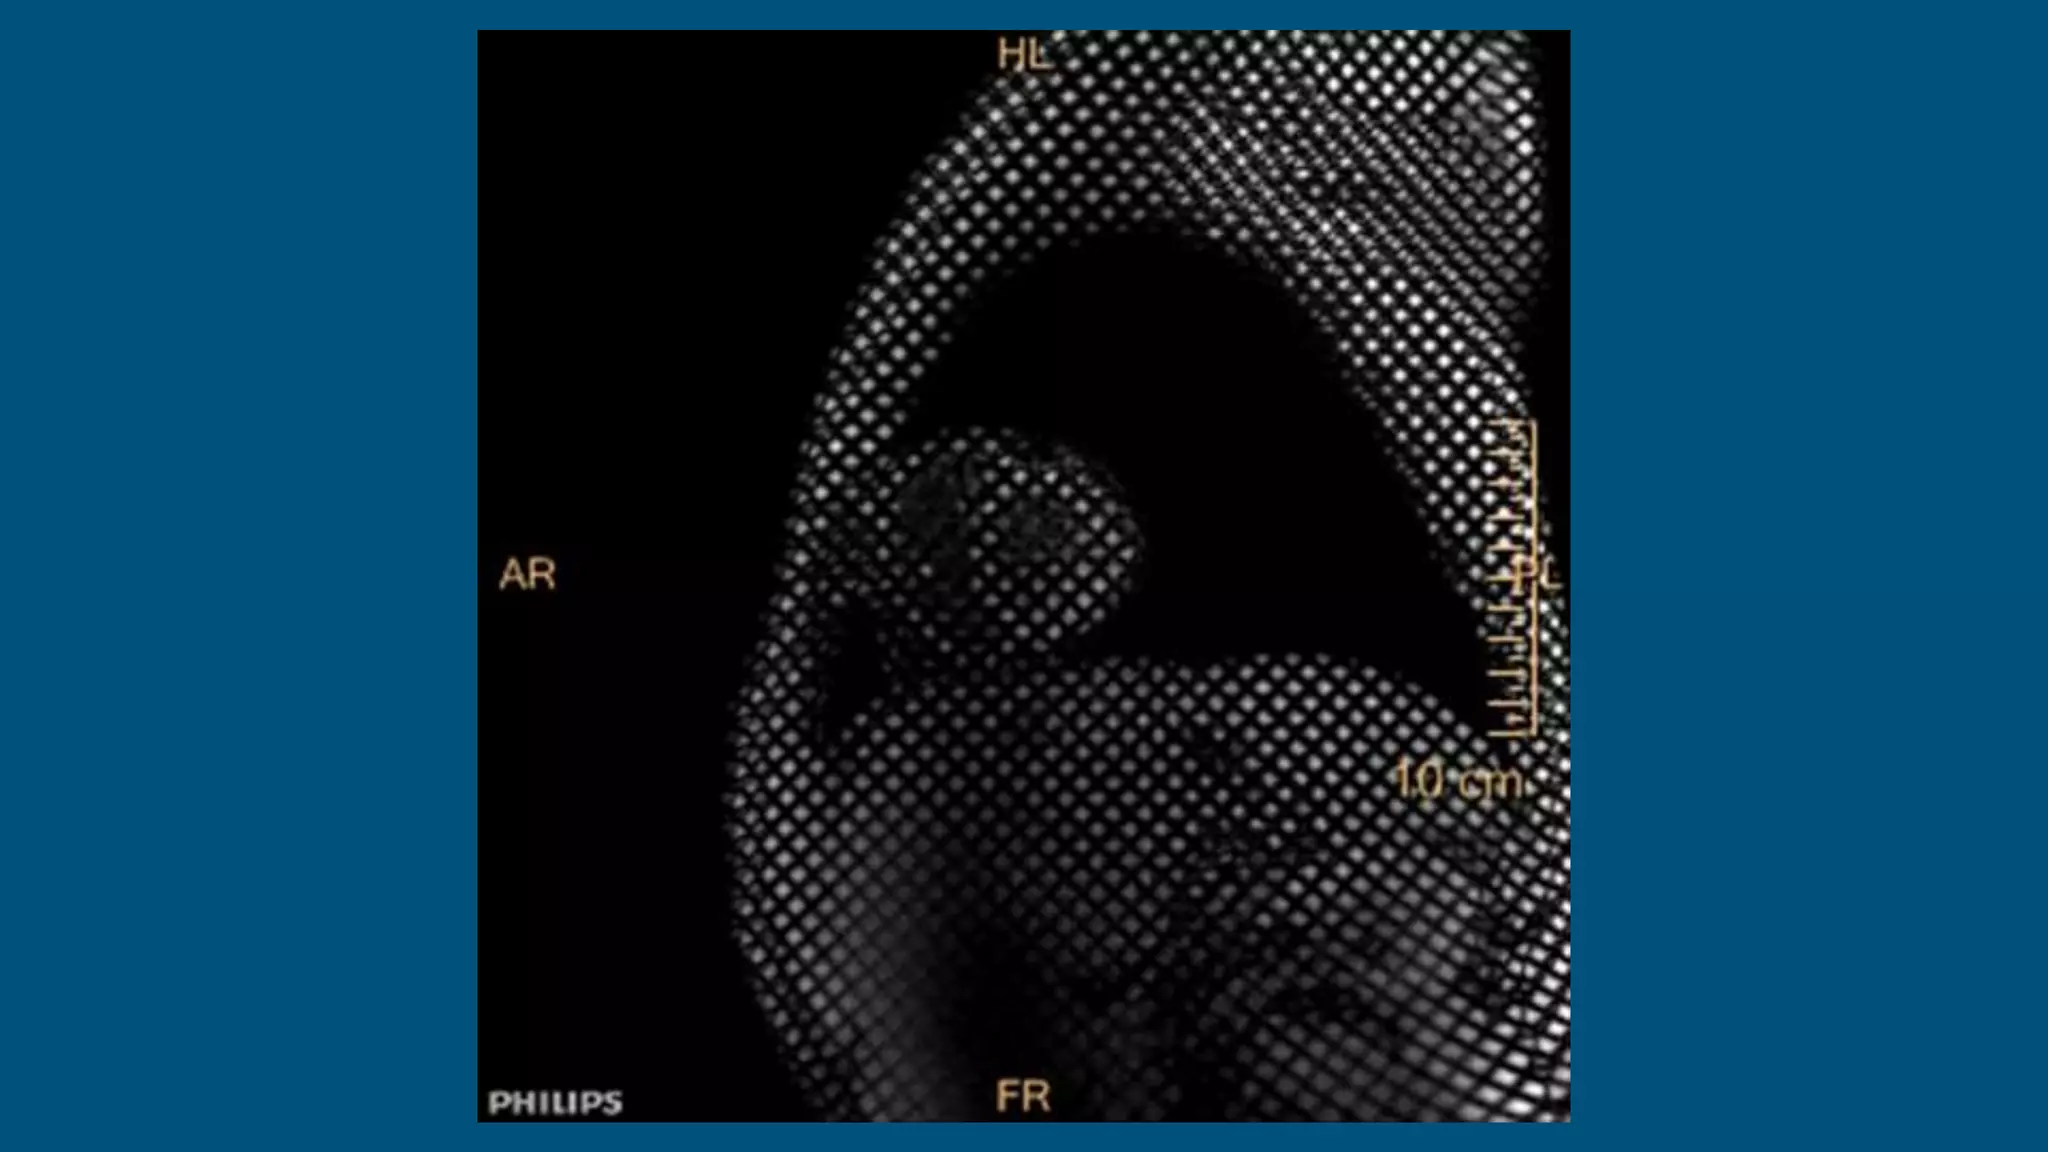

The patient is an 18-year-old male who presented with fever, abdominal pain, and dark urine 6 weeks ago and was diagnosed with mononucleosis. Further imaging found incidental pericardial calcifications. The patient has since developed dyspnea and palpitations. On exam, jugular vein distention and hepatosplenomegaly were present, as well as a precordial knock. Imaging and testing showed calcific constriction of the pericardium consistent with calcific pericarditis.